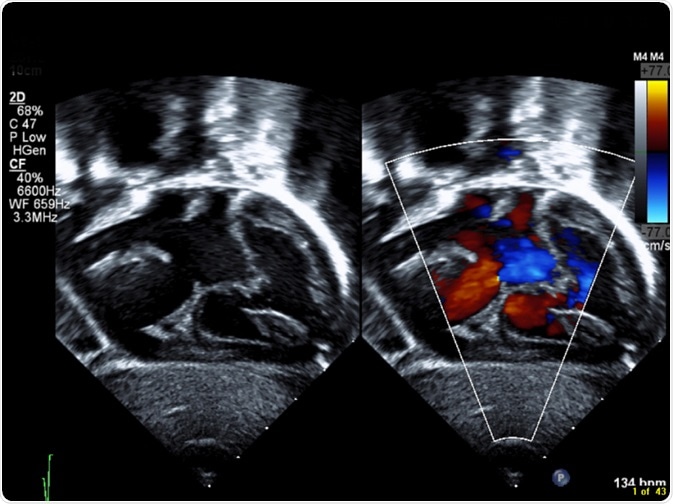

Septal defects are colloquially known as “holes” in the heart. These arise when there are abnormal connections between any of the heart’s chambers, which normally only communicate via a system of valves that open and close with contraction of the heart.

Septal Defect

Image Credit: Sumer McNitt/Shutterstock.com